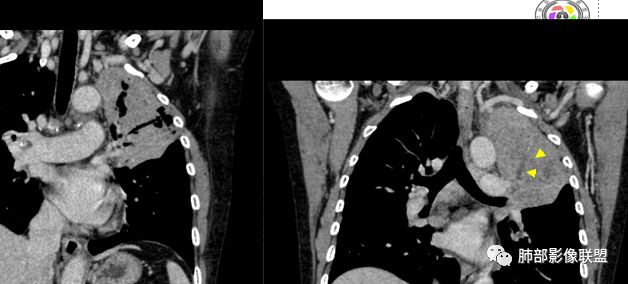

整个上叶尖后段阻塞性肺不张的表现,从强化来看没有异常结节状或肿块样强化,肿块内部点状钙化、纵隔多发小淋巴结、下叶背段有树芽征,整体来看支持肺结核,让人不放心的是最后一幅冠状位重建的图像尖后段支气管堵了,而且有轻度的隆起,所以很难除外粘液表皮样癌(女性,鳞癌可能性小),如果是我写报告肯定会建议纤支镜检查

中年女性,反复咳嗽咳痰4月,加重半月,咳嗽,咳黄痰。胸CT:左肺体积缩小,左肺上叶病变,病灶内可见支气管征,病灶边缘可见棘突样改变,病灶周围可见结节状卫星灶,纵隔可见淋巴结肿大,部分淋巴结可见钙化灶。增强CT病灶内可见低密度坏死区,冠状位病灶内支气管可见扩张,病灶整体呈收缩,考虑患者为良性慢性感染性病变,结核?放线?,建议支气管镜检查。

考虑结核伴混合感染。中青年女性,持续低热、不正规抗感染症状加重。左上肺低密度肿块,左上固有段支气管未显影(结核侵蚀干酪样坏死),左上舌段支气管通畅但增厚变形。左下肺树芽征新发支气管播散。鉴别:粘液腺癌

左上叶实变不张,膨胀生长,上叶开口阻塞?,病灶内支气管扩张,明显延迟强化,内见低密度灶及点状钙化,周边见小叶间隔增厚丶结节,右斜裂结节

左上胸缩小,但是左上叶部分实变,边缘膨隆,内部有含气支气管,粘液栓,近端支气管堵塞

前端支气管通畅,部分稍扩张,走形自然

实变区支气管内粘液栓明显

上叶支气管堵塞处稍萎缩、凹陷,附近壁增厚,内可见小点状钙化

看这些钙化

前壁不厚,附近钙化灶太多,所以觉得结核一定要考虑,加上树芽征,就更支持。

支气管因为软骨,密度偏高,从这连续性看,支气管这一段的壁不厚,只是周围有病灶。

支气管壁软骨存在且连续,没有被破坏掉,支气管壁局部通畅,提示支气管壁没破坏,那么近端支气管癌肿不考虑。远端有树丫征,病灶周围很多钙化,所以结核一定有。